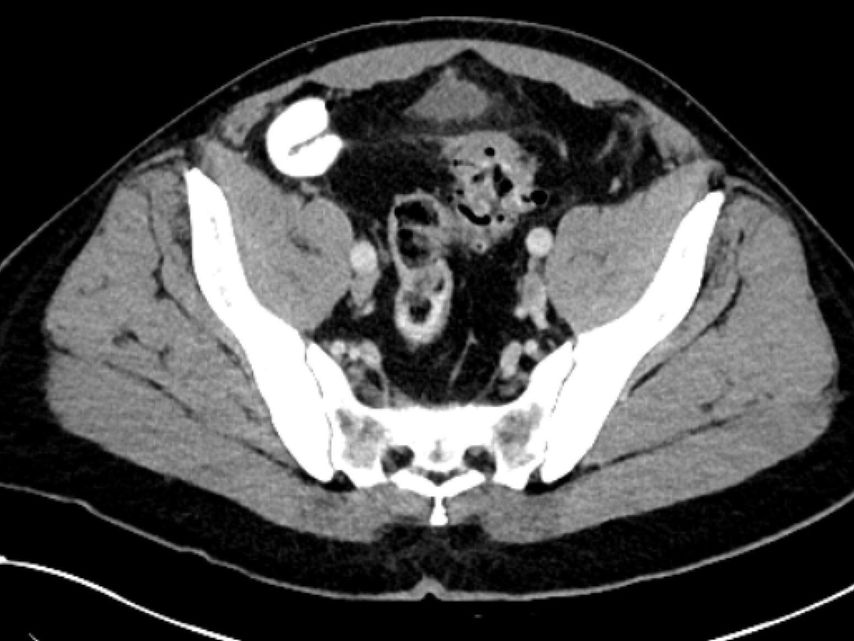

diverticulite compliquée aiguë (type 2a–c) (Fig. 2 et 3) et

maladie diverticulaire chronique (maladie diverticulaire symptomatique récidivante ou persistante; type 3a–c) (Fig.4).

La diverticulite compliquée aiguë de type 2 distingue, avec les types 2a et 2b, la perforation couverte avec micro-abcès (≤3cm) et macro-abcès (>3cm). Le type 2c désigne la perforation libre avec péritonite purulente ou fécale. La diverticulite compliquée aiguë nécessite une hospitalisation et doit être traitée par une antibiothérapie. Si l’apport en liquides est insuffisant, il convient de substituer les liquides par voie parentérale. Un apport alimentaire adapté à la situation peut être mis en place. Contrairement au macro-abcès de type 2b, le micro-abcès de type 2a n’est pas accessible au drainage interventionnel. Si le traitement est efficace, il n’y a pas forcément d’indication d’une opération élective. Il convient de noter que le risque de récidive est corrélé à la taille de l’abcès. Les abcès rétropéritonéaux ou péricoliques (>3cm) peuvent faire l’objet d’un drainage interventionnel. Après une thérapie conservatrice ou interventionnelle réussie de la diverticulite, une opération peut être proposée dans l’intervalle sans inflammation, après environ 6 semaines.

La perforation libre de type 2c constitue une situation d’urgence et il convient d’opérer dès que le diagnostic est posé. Il y a urgence, car l’absence de nettoyage du foyer est associée à une létalité de 40 à 85% en cas de sepsis abdominal.3 Il faut viser une résection rectosigmoïdienne avec anastomose, avec ou sans iléostomie de protection. Selon la situation, une résection avec discontinuité selon Hartmann peut être réalisée en alternative.4